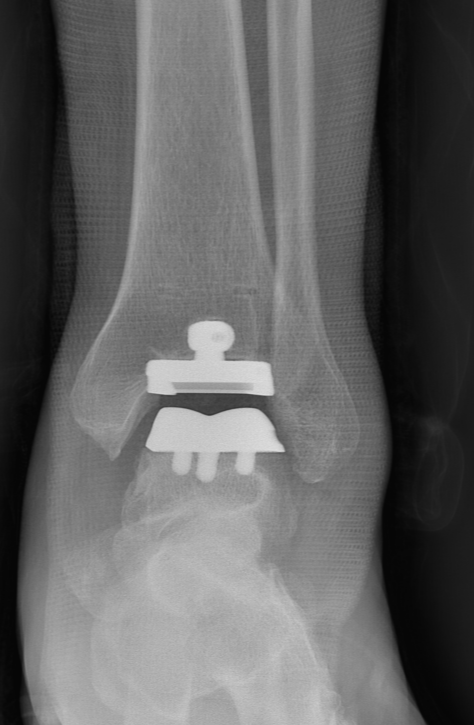

武勇主任团队给他做了3D打印导板辅助下人工全踝关节置换术。

术后正位X线